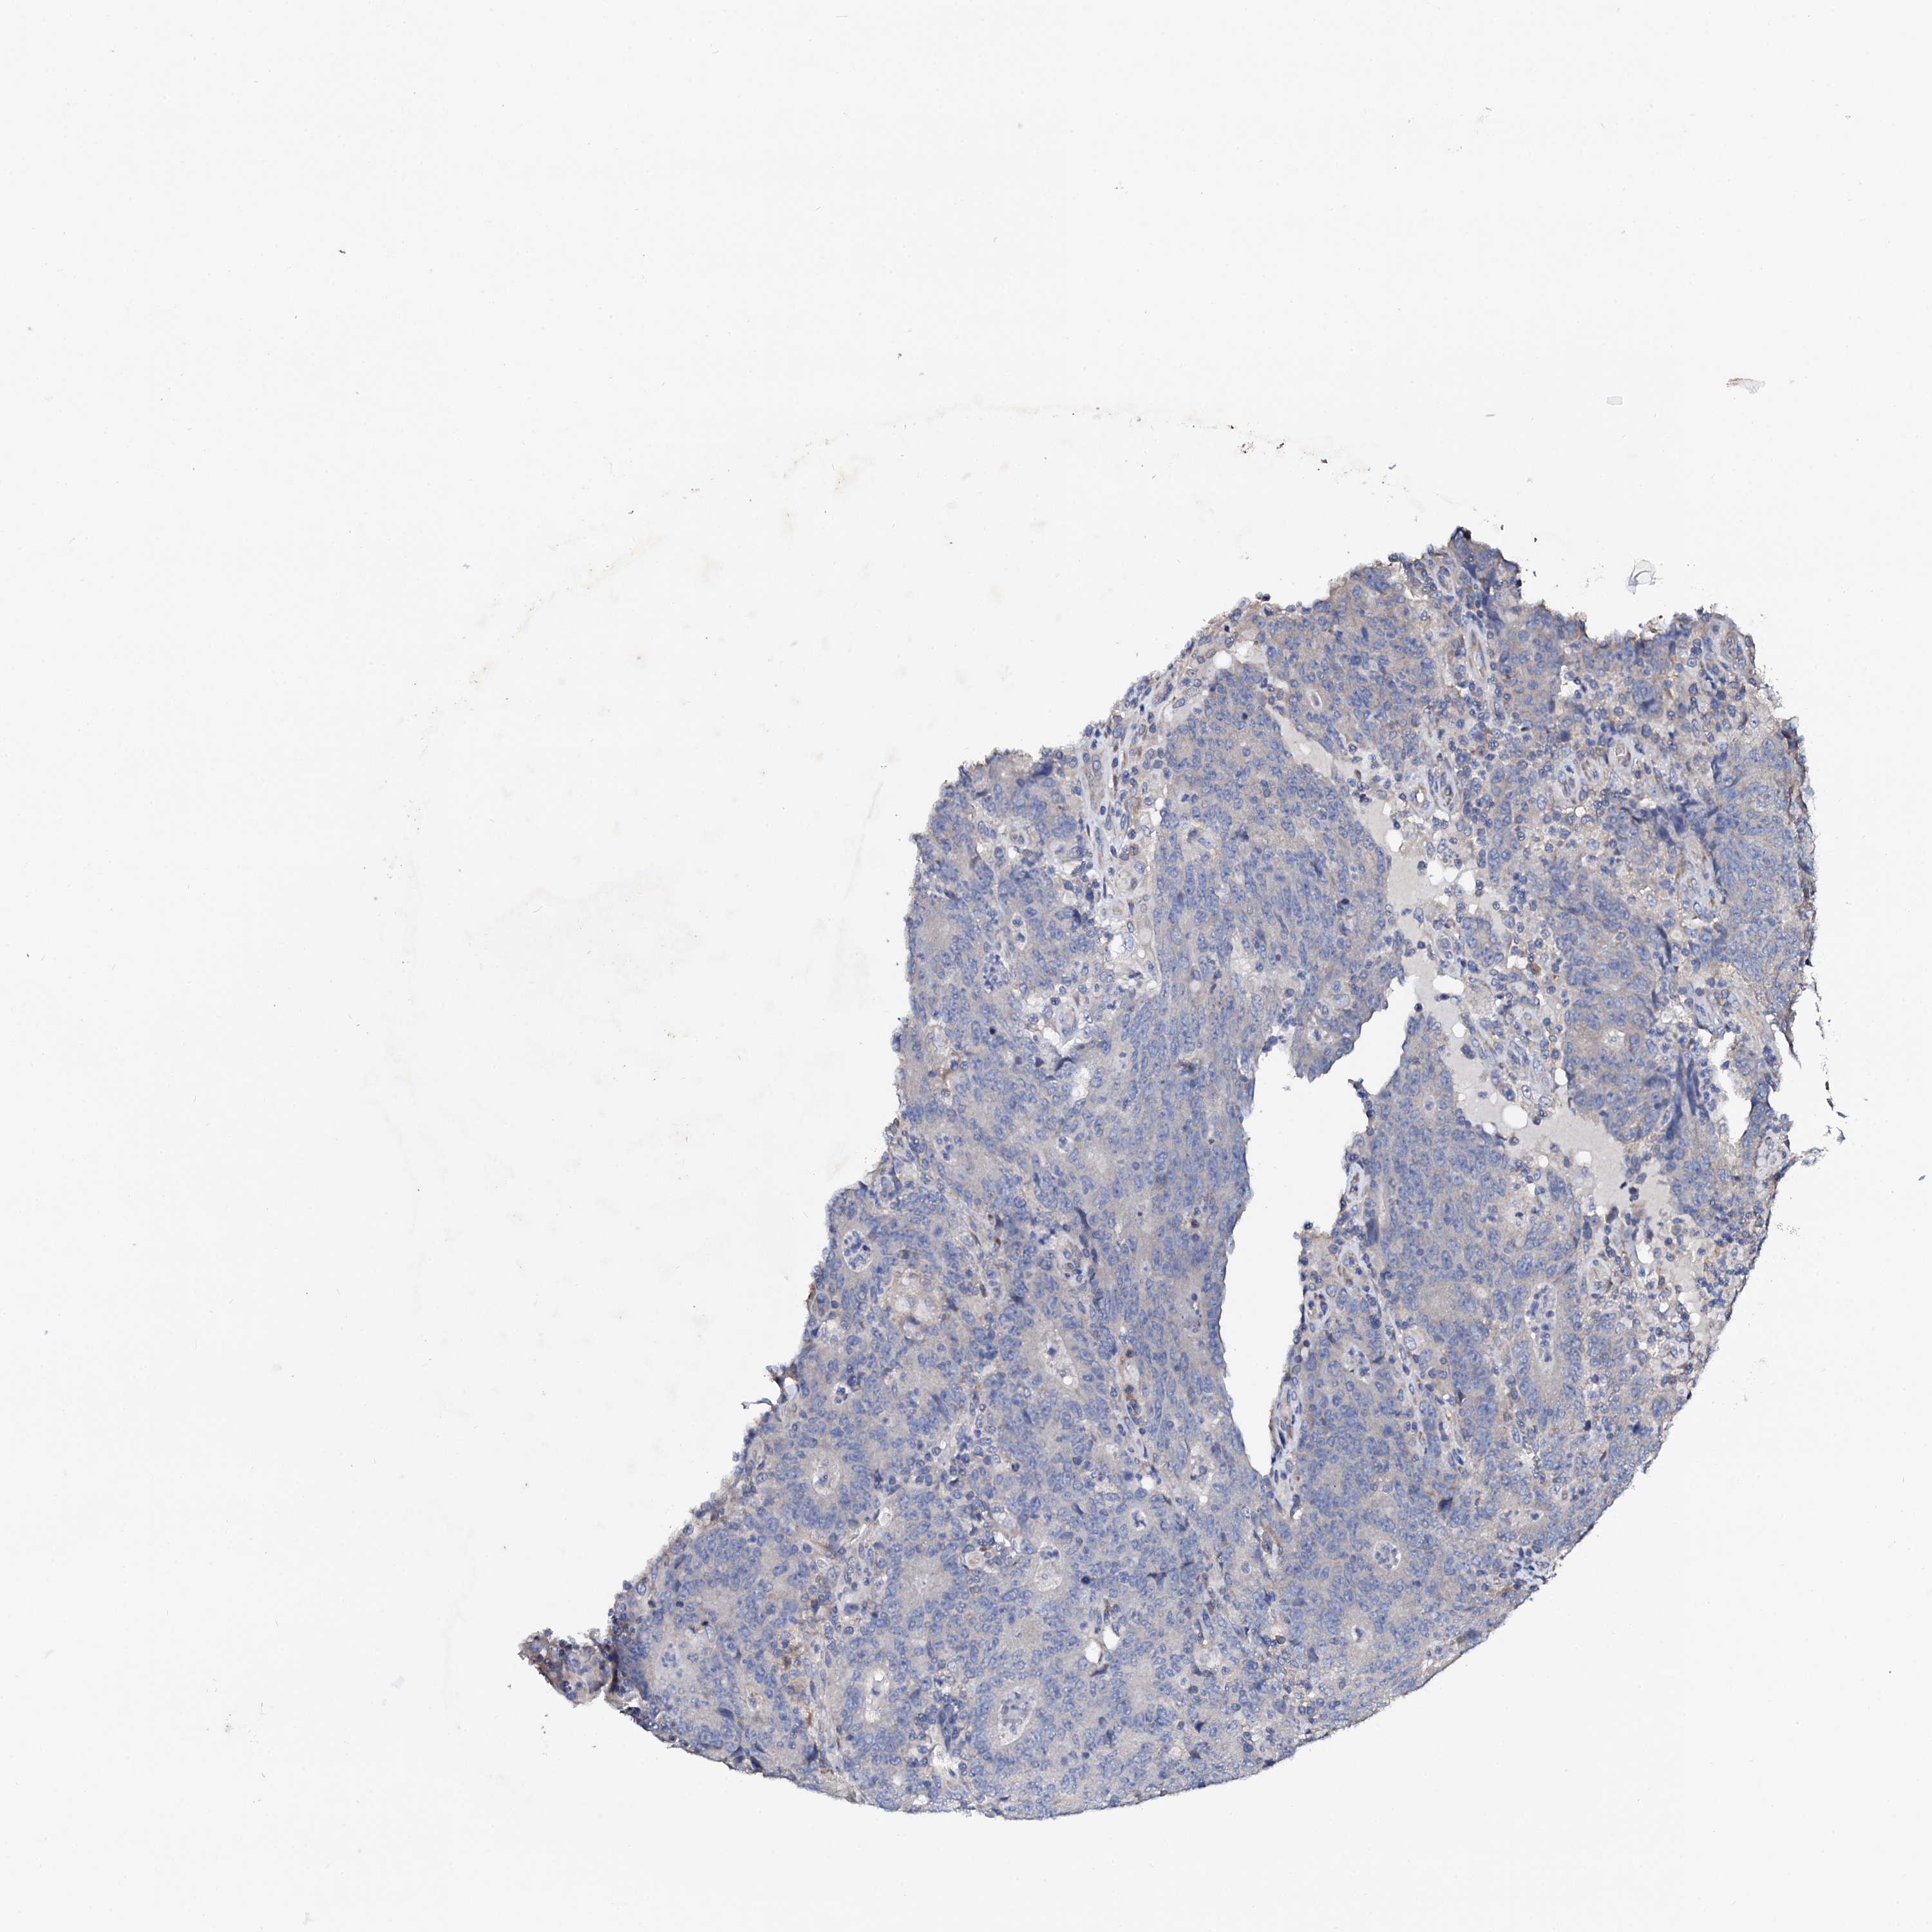

CANCER COLORECTAL CANCER Show tissue menu

Colorectal cancer

Human cancer

Colon adenocarcinoma

NUP58 is not prognostic in Colon Adenocarcinoma (validation)